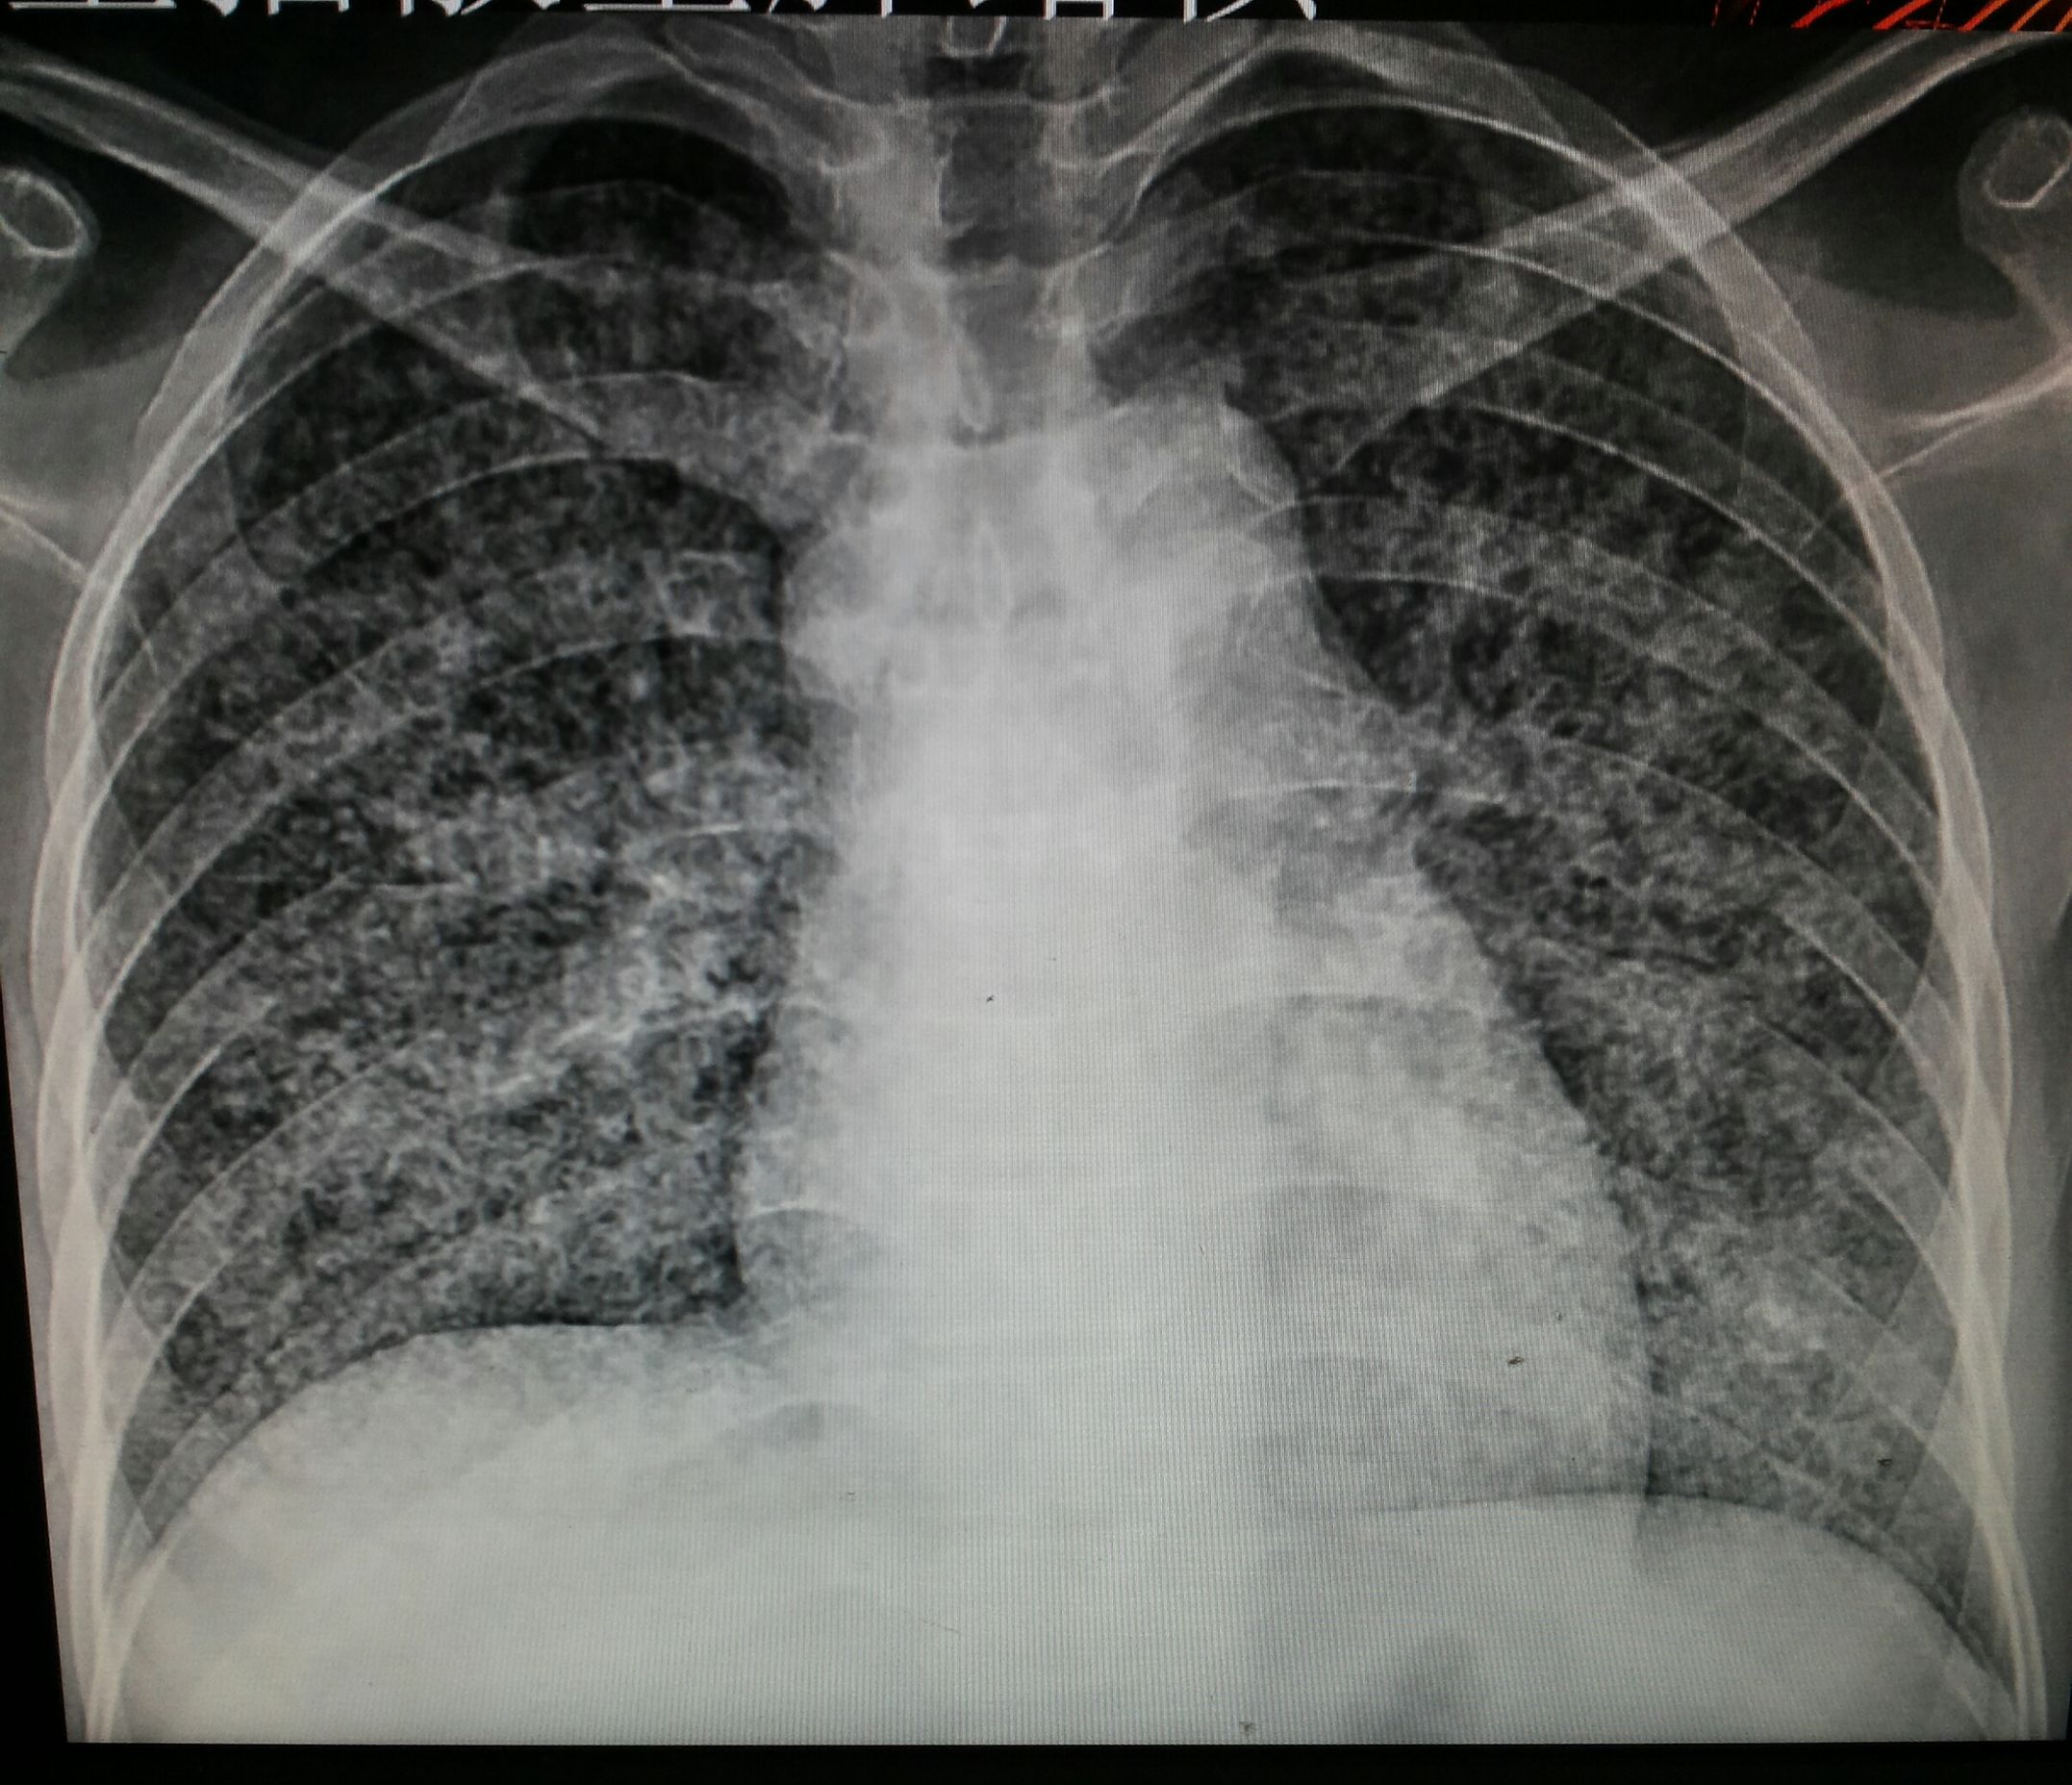

图片来源于网络

根据美国放射协会和妇产科协会的数据。胎儿受到的照射剂量高于5000mrad才会引起胎儿的损伤。但一次胸部拍片胎儿受到的照射剂量是0.02-0.07mrad。腹部平片胎儿受到的照射剂量是100mrad。肾盂静脉造影胎儿受到的照射剂量大于1000mrad。钡灌肠造影时,因为需要多次连续成像胎儿受到的照射剂量约2000-4000mrad。临床上已经较少用钡灌肠造影而是更长做胃肠镜。

CT检查放射剂量略大。但也和检查部位有关。如果是盆腔CT,胎儿受到了照射剂量是可以达到1500mrad。而其它部位肺部、头部因为远离盆腔。胎儿受到的照射剂量远远低于这个水平。近年来CT技术不断改进,医生可以使用低剂量CT。低剂量CT检查盆腔,胎儿接受的放射线剂量只有250mrad。你看这么多的检查项目都没有达到胎儿损伤的剂量。所以单次接受放射线检查剂量都非常的低,尤其是远离盆腔的检查不够以造成胎儿的损伤。